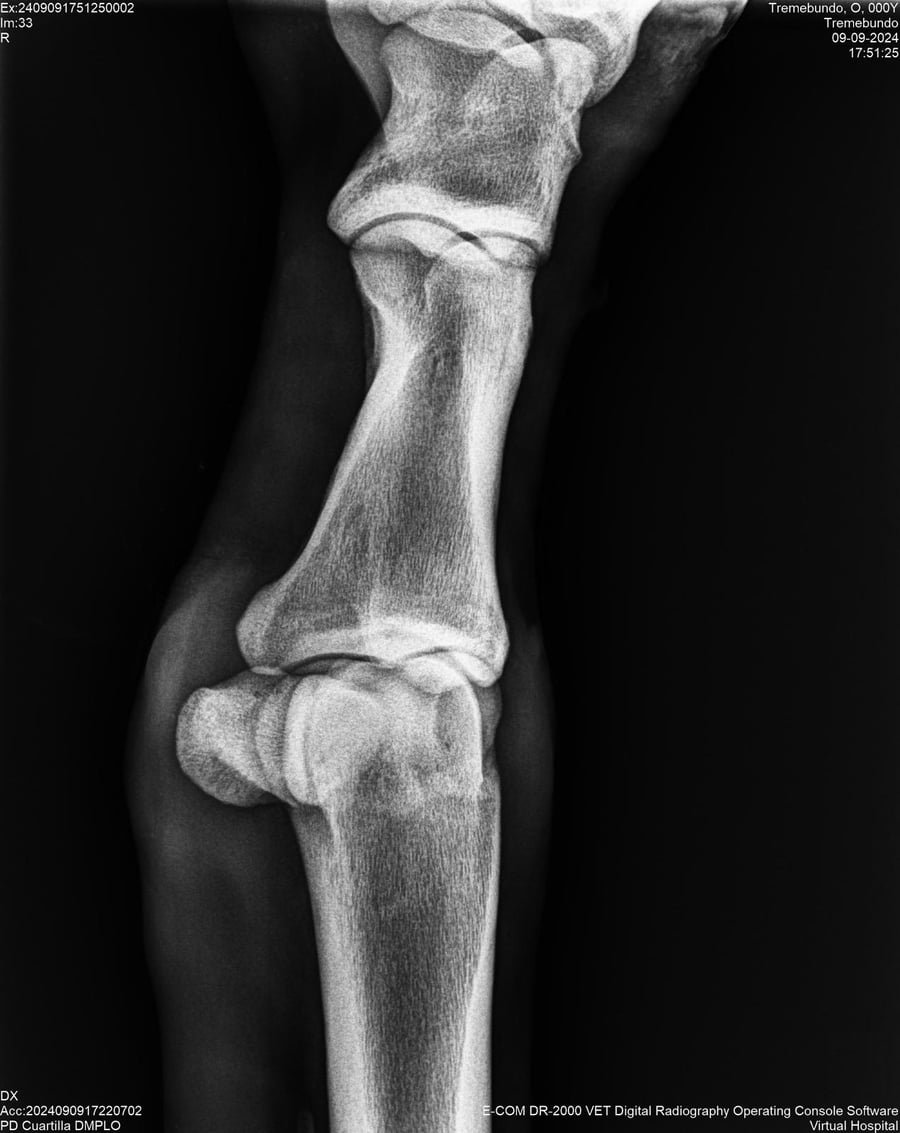

LOTE 37, TREMEBUNDO

Identificador: #291140-

Generacion 2022